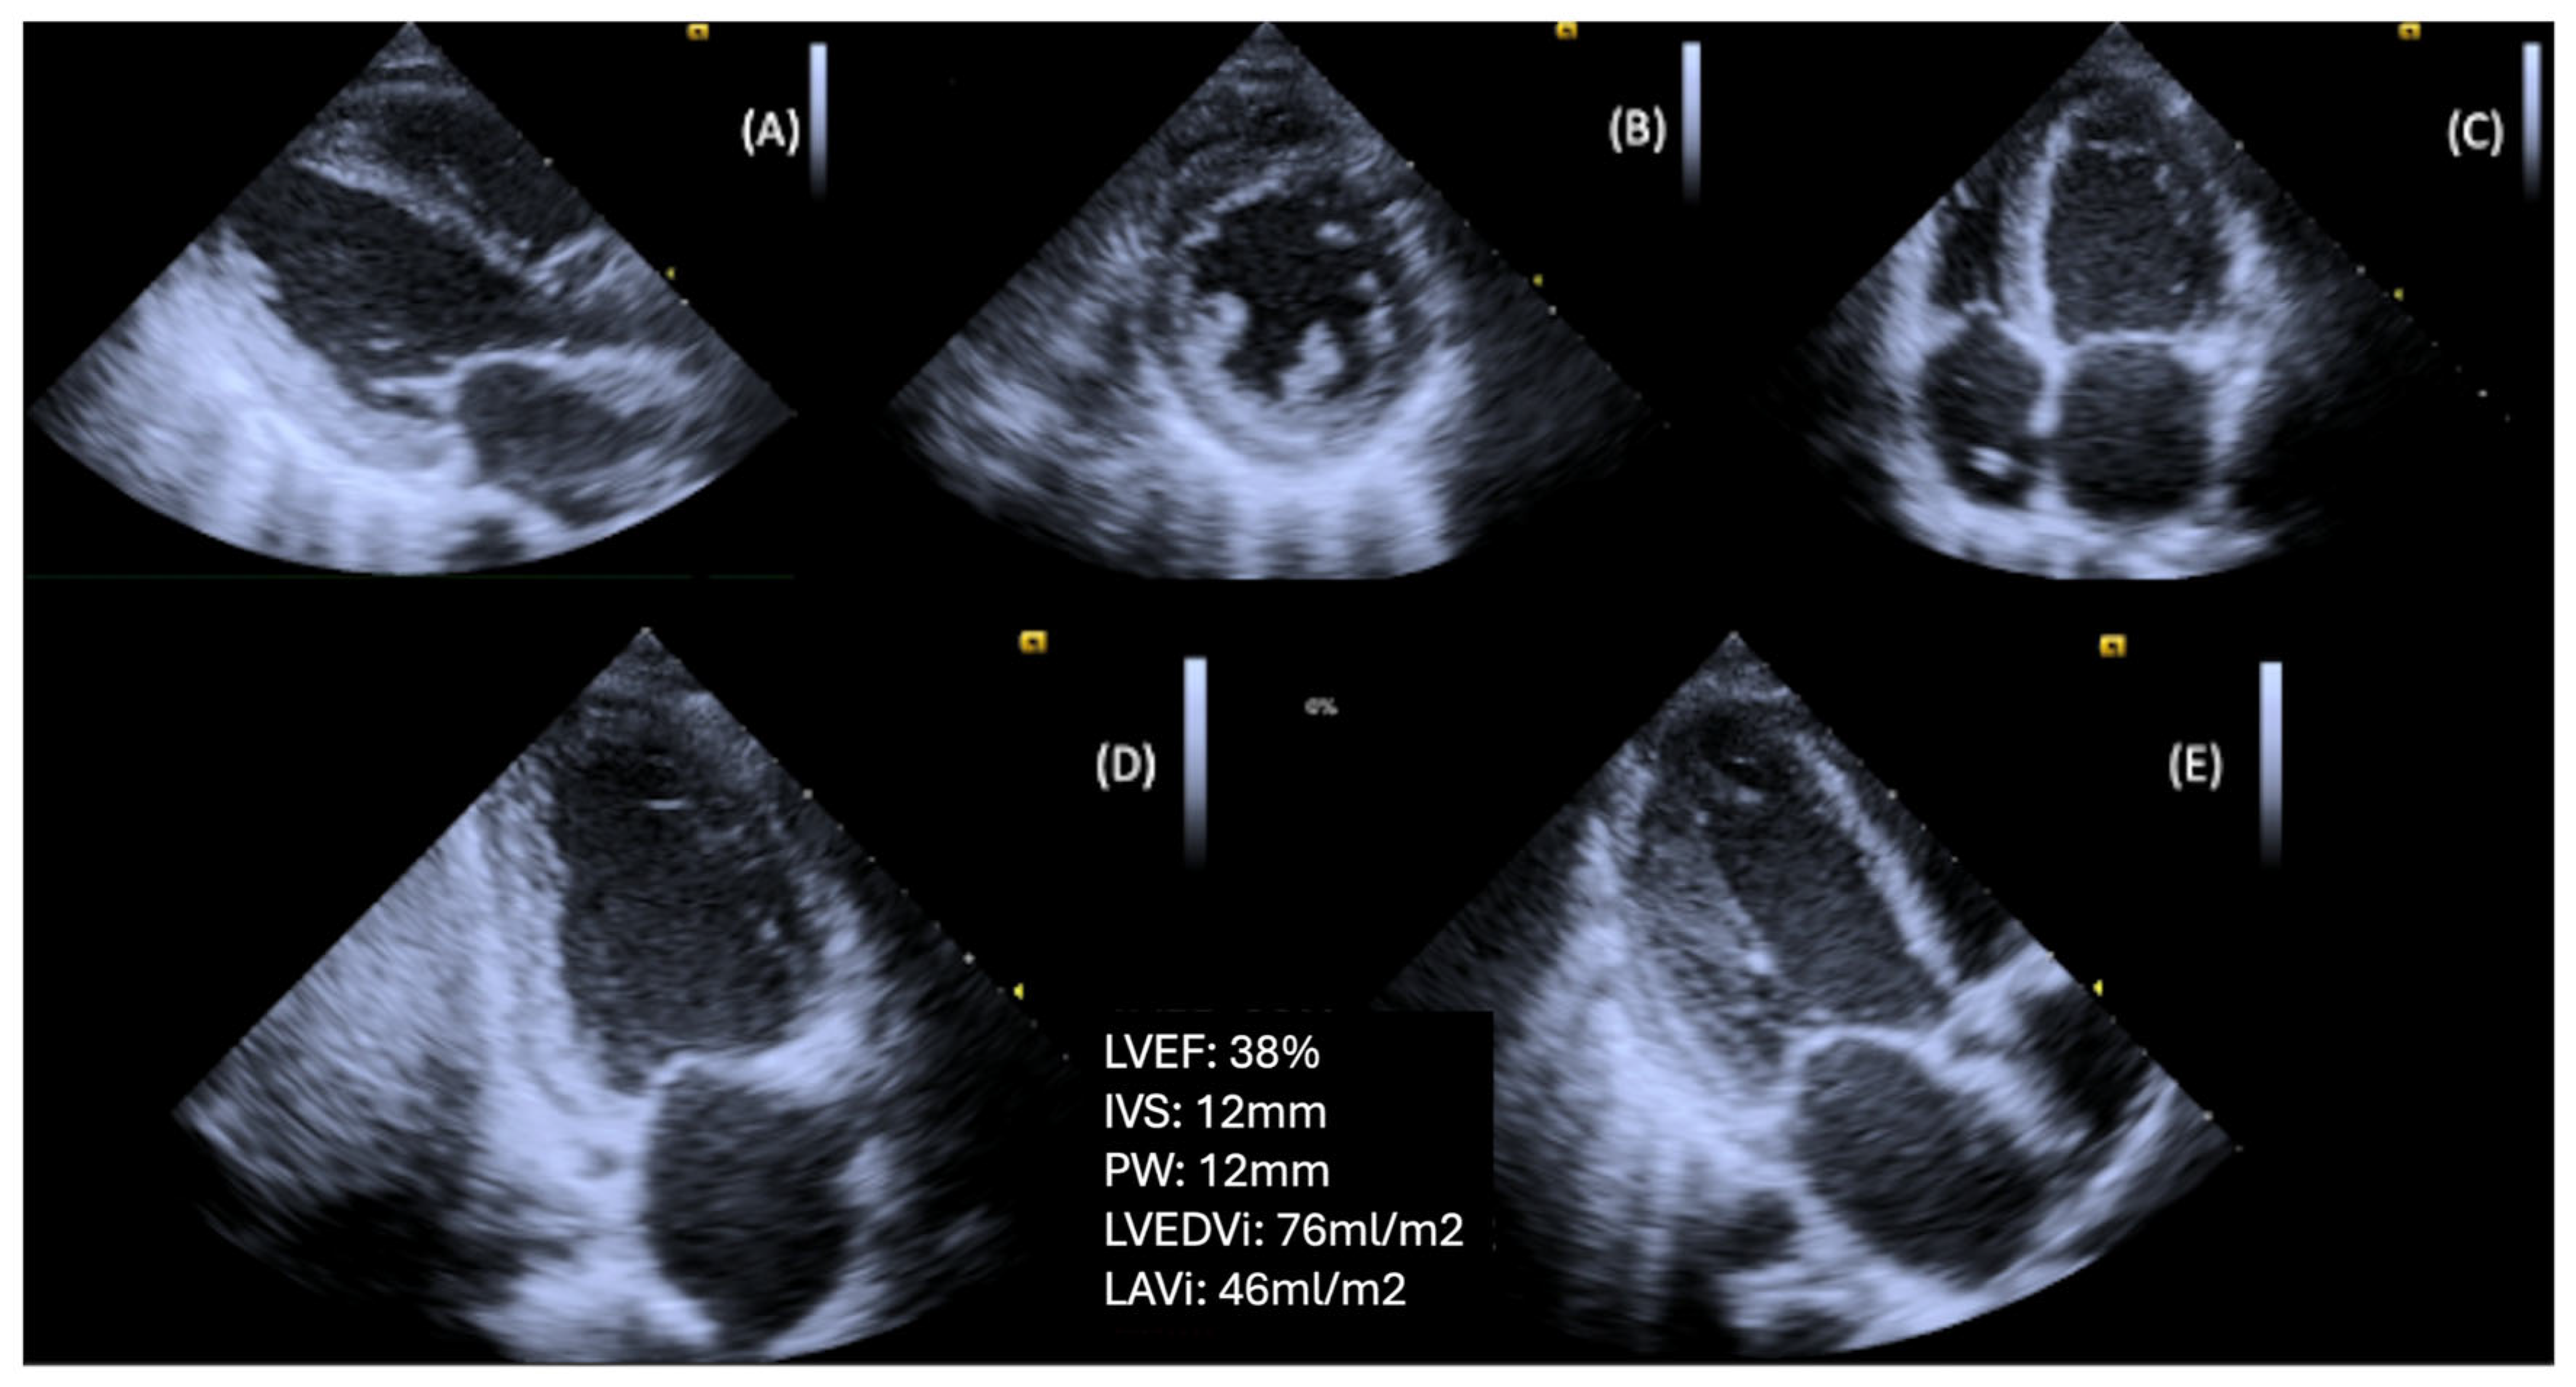

Exercise stress echocardiography (ESE) is a valuable tool for unmasking diastolic dysfunction in patients with unexplained dyspnea and/or fatigue, particularly when the diagnosis remains uncertain due to inconclusive resting echocardiographic findings. The 2020 HFA–PEFF diagnostic algorithm recommends the use of ESE to confirm the diagnosis of HFpEF in cases of intermediate HFA-PEFF score [4,5,86]. The latter score is initially calculated from resting echocardiography parameters and natriuretic peptides levels. The addition of ESE is to reveal exaggerated elevations in LVFP and pulmonary artery systolic pressure (PASP) on exertion.

In clinical practice, ESE is commonly performed using a semi-supine ergocycle protocol with incrementally increasing workload (typically 25-watt increments every 2 min), enabling optimal image acquisition during each exercise stage [88,89,90]. Alternatively, upright bicycle and treadmill protocols are also used, particularly in centers without access to supine ergometry. However, these may limit real-time image acquisition, which can introduce variability due to rapid heart rate recovery [91].

During exercise, a rise in E/E′ and an increase in TR peak velocity (TRVpeak) are often observed in patients with HFpEF, reflecting an abnormal surge in LVFP and PASP, respectively. As heart rate rises, the impaired relaxation in diabetes leads to a disproportionate rise in LVFP and pulmonary pressures, exposing diastolic abnormalities not evident at rest [91,92,93]. Notably, according to the ESC consensus criteria, an exercise E/e′ ≥ 15 and/or TRVpeak > 3.4 m/s are indicative of HFpEF during stress [90]. Moreover, ESE may show an inadequate increase in stroke volume despite rising LVFP, differentiating cardiac limitations from non-cardiac causes of exercise intolerance (Figure 6).